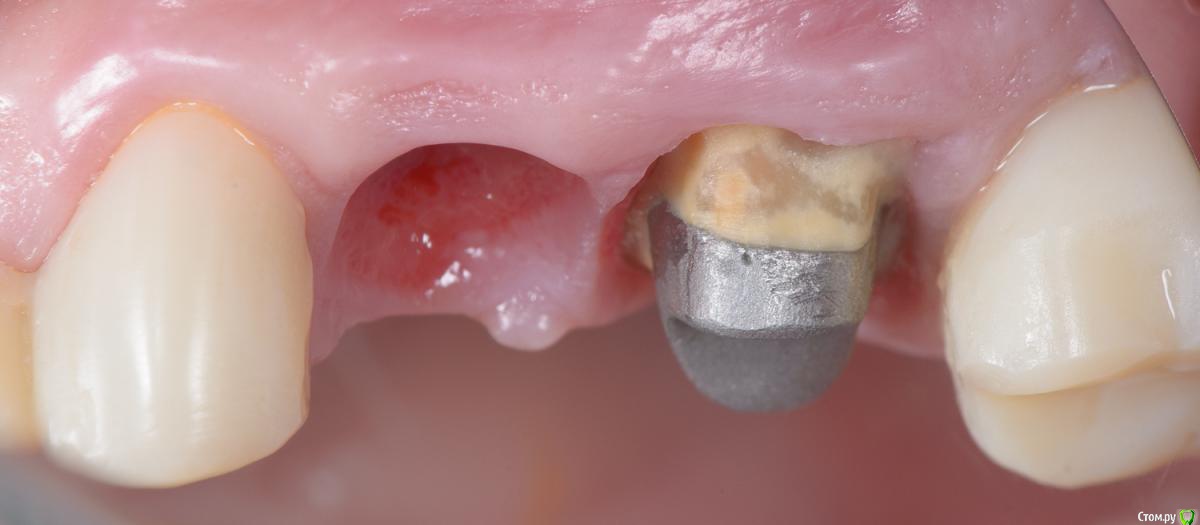

Популярный пост Mane Опубликовано 8 февраля, 2015 Популярный пост Поделиться Опубликовано 8 февраля, 2015 Зафиксировал в субботу. Собственно удалось размоделировать десну просто временной коронкой с заданным профилем прорезывания. Но для этого необходимо было выполнить ряд условий. Каких, доктора? http://i1218.photobucket.com/albums/dd412/Edikn73/emergence%20profile/Emergenceprofile001_zps040f2603.jpg http://i1218.photobucket.com/albums/dd412/Edikn73/emergence%20profile/Emergenceprofile002_zpsaa7acb0b.jpg http://i1218.photobucket.com/albums/dd412/Edikn73/emergence%20profile/Emergenceprofile003_zps259f0885.jpg http://i1218.photobucket.com/albums/dd412/Edikn73/emergence%20profile/Emergenceprofile004_zps6a15b901.jpg http://i1218.photobucket.com/albums/dd412/Edikn73/emergence%20profile/Emergenceprofile005_zps51a41bc2.jpg http://i1218.photobucket.com/albums/dd412/Edikn73/emergence%20profile/Emergenceprofile006_zps3c83a34d.jpg http://i1218.photobucket.com/albums/dd412/Edikn73/emergence%20profile/Emergenceprofile007_zpsba4d3d78.jpg 26 Ссылка на комментарий

carloss Опубликовано 8 февраля, 2015 Поделиться Опубликовано 8 февраля, 2015 (изменено) хорошо)) немного спорен правда дизайн вкладки вестибулярное, восстановленный контакт между зубами)) а абатмент литой или фрезеруемый.. в смысле есть уверенность в точности соединения с имплантатом? Изменено 8 февраля, 2015 пользователем carloss 1 Ссылка на комментарий

Mane Опубликовано 8 февраля, 2015 Автор Поделиться Опубликовано 8 февраля, 2015 хорошо)) немного спорен правда дизайн вкладки вестибулярное, восстановленный контакт между зубами)) а абатмент литой или фрезеруемый.. в смысле есть уверенность в точности соединения с имплантатом? фрезеруемый цельный одним куском вместе с внутриимплантной частью. есть уверенность. спасибо Ссылка на комментарий

Mane Опубликовано 10 февраля, 2015 Автор Поделиться Опубликовано 10 февраля, 2015 По поводу профиля прорезывание интересен Ваш протокол. Менялся ли ФДМ на более широкий, делались ли насечки на десне во время фиксации времяхи? Во первых - это заглубление платформы импланта - от будущего зенита до платформы - 3,5 мм . если этого не сделать - ничего не полуитсяпосле тонкого фдм зафиксировал временную коронку с небольшим надрезом по контактам. отдыхала с времянкой 1,5 мес.далее вы видели 1 Ссылка на комментарий